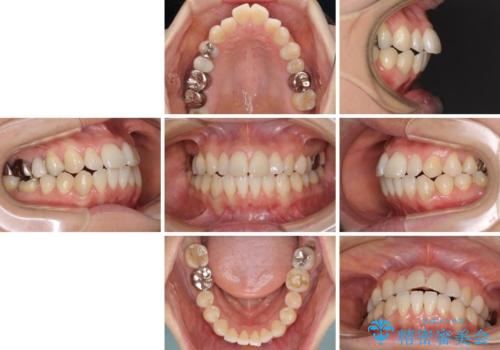

- 捻れた前歯と目立つ銀歯を気にして来院された患者様です。

歯列不正は軽微であったため、インビザライン・ライトにて改善することとしました。

左下大臼歯は根管治療が必要であったため、矯正治療前に根管治療を行い、その後矯正治療を行うこととしました。

矯正治療後には期にある銀歯を全てセラミッククラウンなどで補綴治療することとしました。

インビザライン・ライトによる矯正治療であったので、時間をかけずに治療を終えることができました。

口を開ける度に目立っていた銀歯もセラミックで自然な口元の印象となりました。